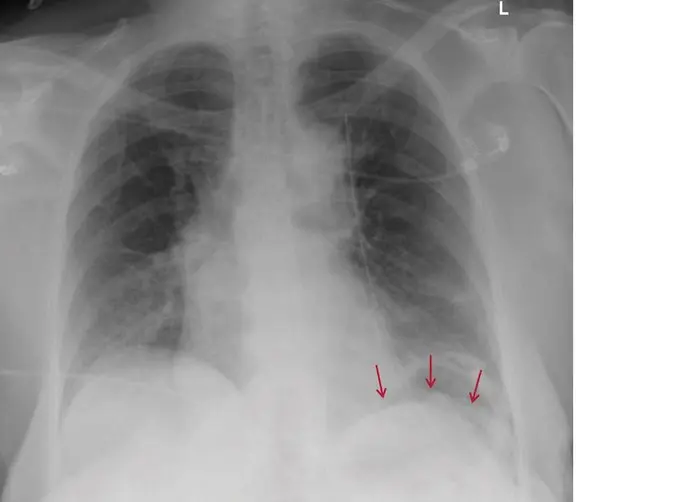

- Röntgenaufnahme des Brustkorbs: Eine Röntgenaufnahme des Brustkorbs zeigt, ob das Zwerchfell auf einer oder beiden Seiten höher steht als normal.